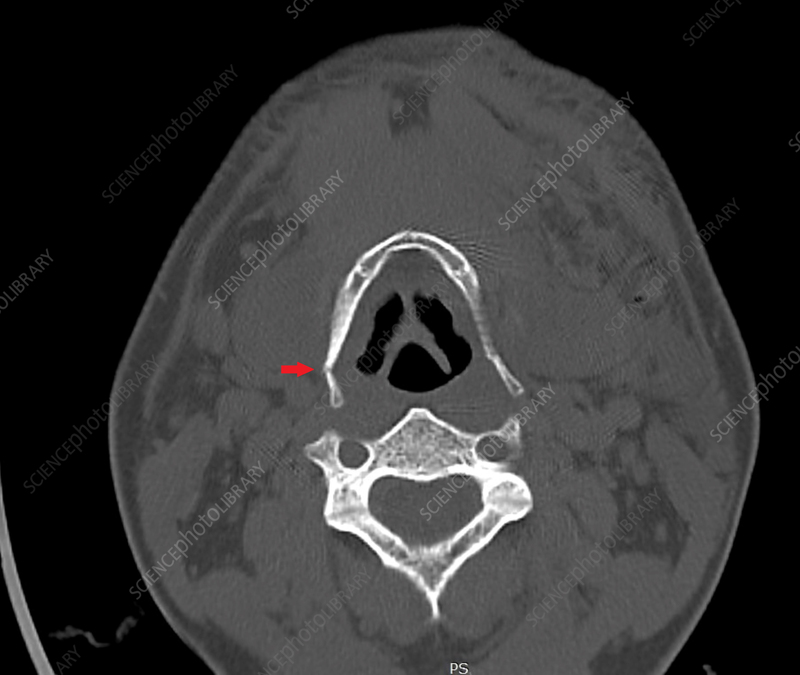

What structure is the arrow pointing to

Hyoid